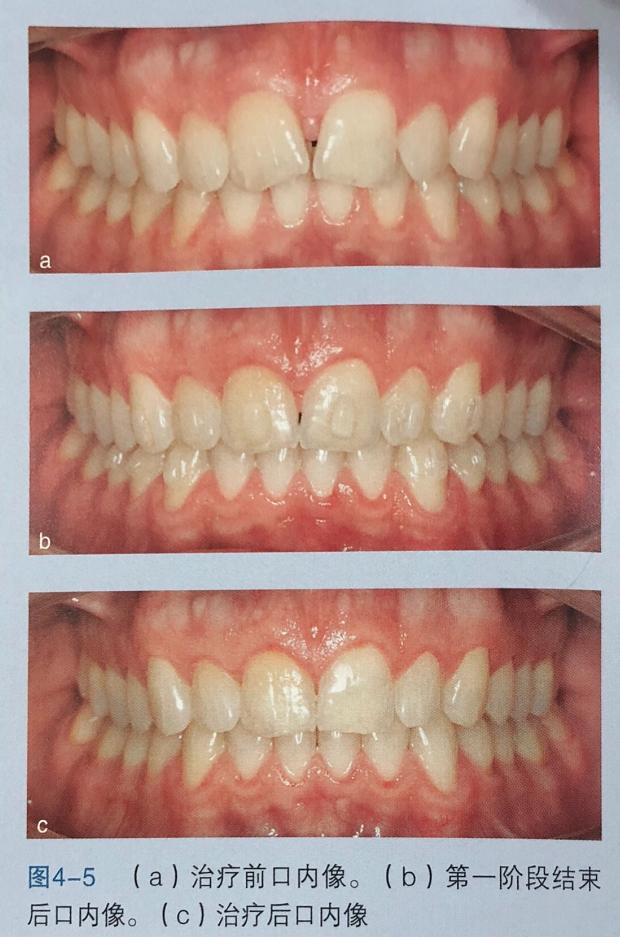

口内像

从图中可以看出黑三角和上中切牙间隙已重合上中切牙压根以正轴,其他方面也全部完成。